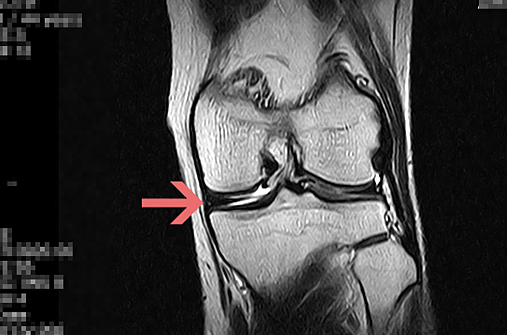

MRI 결과는 충격적이었습니다.

'반월상 연골 파열 증상'

담당 선생님은

연골판이 심하게 찢어져서

관절 내 염증이 진행 중이니

반월상 연골 파열은 보통

수술을 고려해야 한다고 말씀하셨습니다.